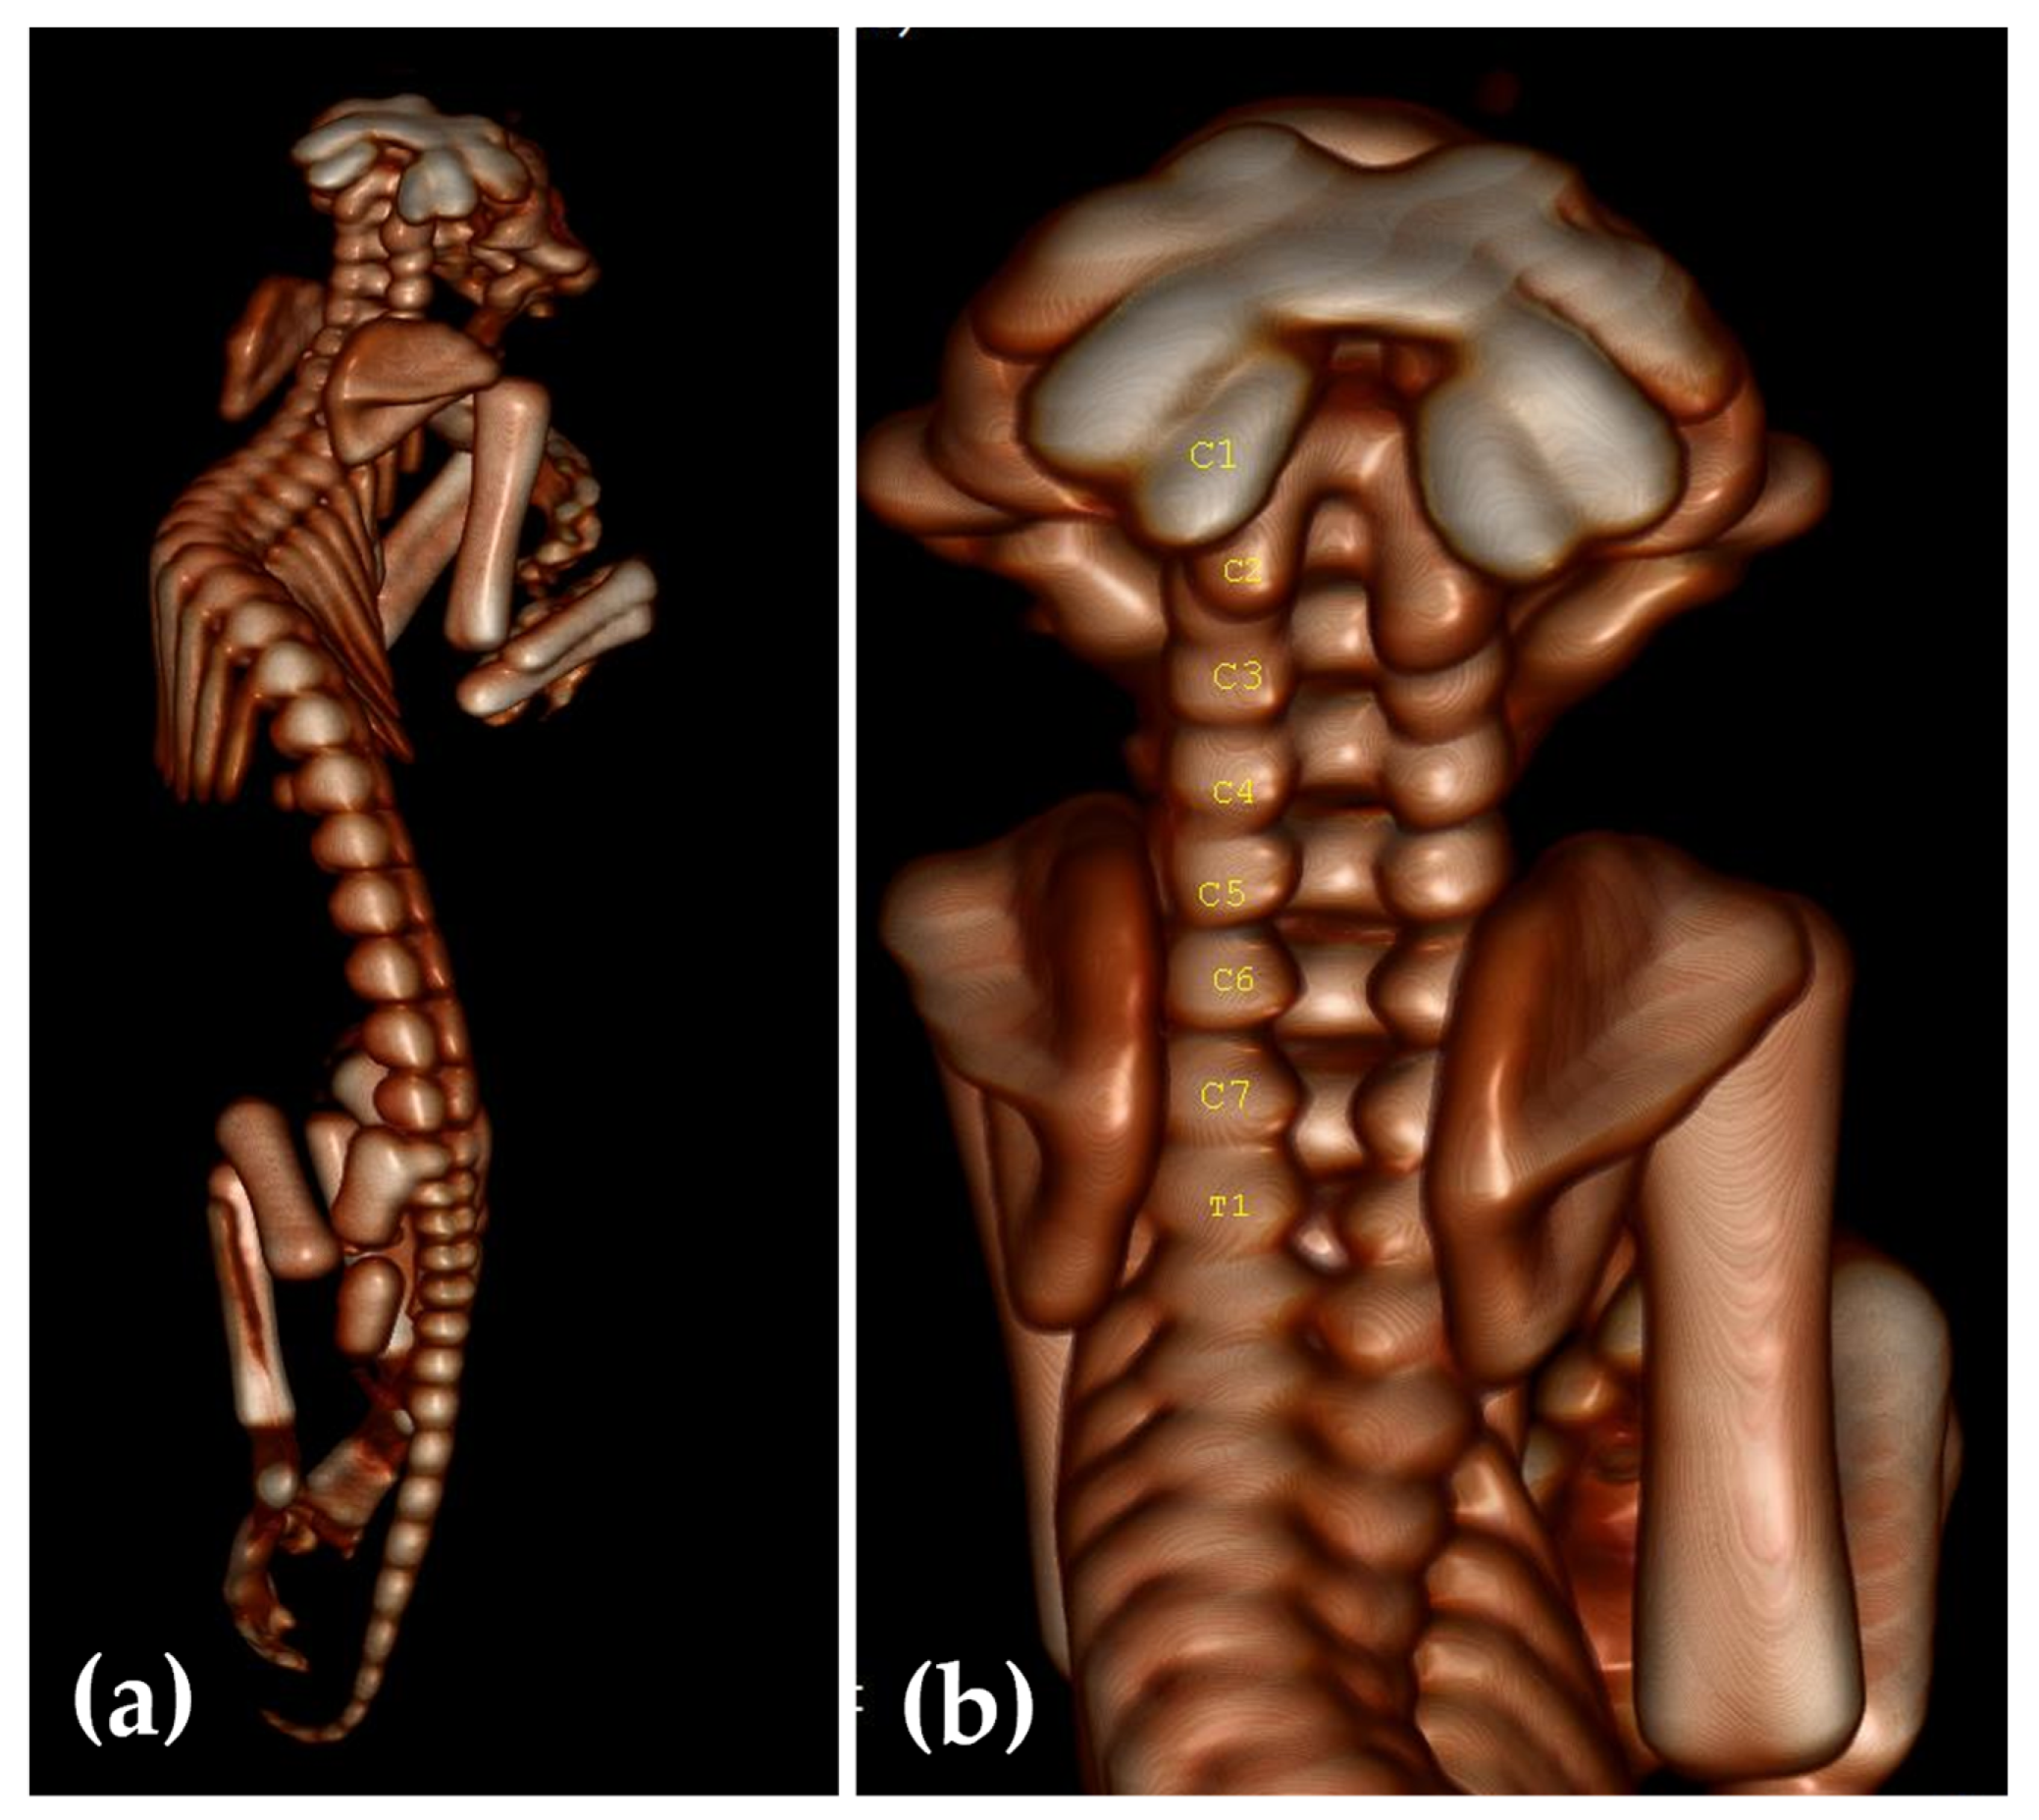

2.3. Computed Tomography Investigation

3. Results

3.1. Clinical Presentation